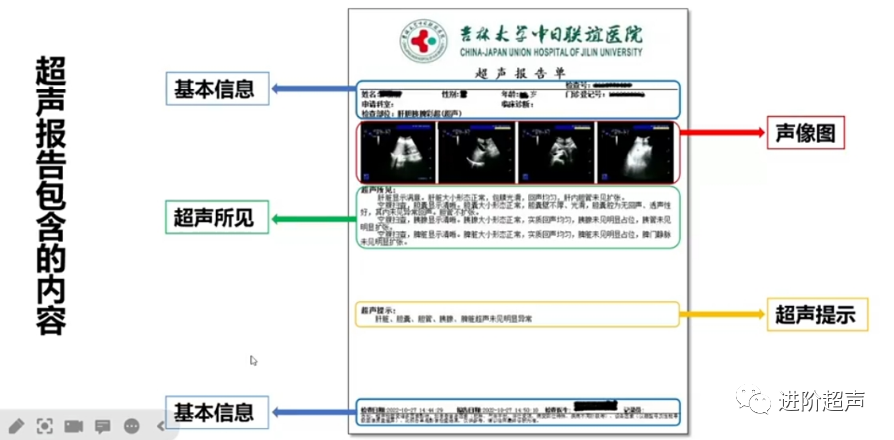

· 胰腺超声诊断规范的

报告书写规范 ·

超声描述:

应包含胰腺显示是否满意,胰腺形态大小是否正常、实质回声是否均匀、胰管是否扩张

胰腺是否存在弥漫性及占位性病变。若可见胰腺病变,应详细描述病变范围及大小、边界、血供情况、与周围结构毗邻关系等击

超声提示:

胰腺无明显病变时,可与腹部其他脏器一起给出阴性提示

胰腺有病变时应明确提示,包括病变来源、病变位置、病变可能的性质。可以提出下一步协助确诊的方法

报告模板示例:

超声所见:

空腹扫查,胰腺显示清晰。大小正常,实质回声胰腺形态、均匀,胰腺未见明显占位,胰管未见明显扩张。

超声提示:

胰腺未见明显异常

示例二

超声所见:

胰腺显示满意。胰腺体、尾部形态、大小正常,实质回声均匀,胰腺钩突部见实质低回声占位,大小2.1cmx3.4cmx2.0cm,形态规则,边界清。CDFI未见明显血流信号,胰管未见明显扩张。

超声提示:

胰腺钩突部实性占位,倾向恶性,建议结合增强影像